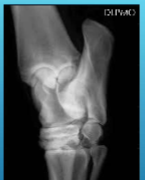

What position was used to take this radiograph

DLPM O

Dorso-Lateral Proximal Medial Oblique

What is this lesion

OCD of the lateral malleolus in horse hock